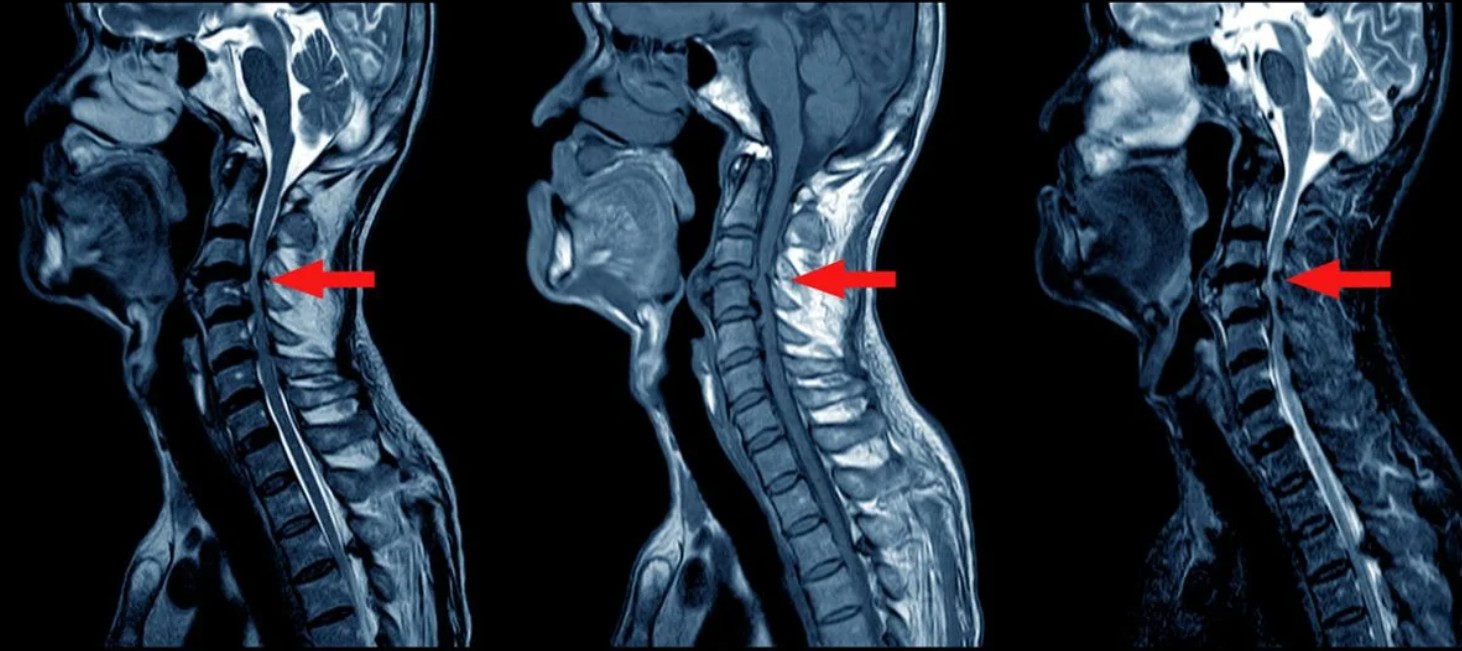

Сьогодні, як і у більшості містах України, в Києві можна пройти магнітно-резонансну томографію (МРТ). Цей сучасний метод діагностики дозволяє отримати детальні пошарові зображення внутрішніх органів, м'яких тканин, кісток та інших внутрішніх структур тіла. Такі знімки дозволяють виявляти хвороби на будь-якій стадії розвитку, призначати відповідне лікування та відслідковувати його ефективність. Завдяки програмі НСЗУ, МРТ безкоштовно можна зробити в Києві. Сьогодні спробуємо розібрати детально, як зробити МРТ безкоштовно Київ та чи є безкоштовне МРТ для військових у Києві.